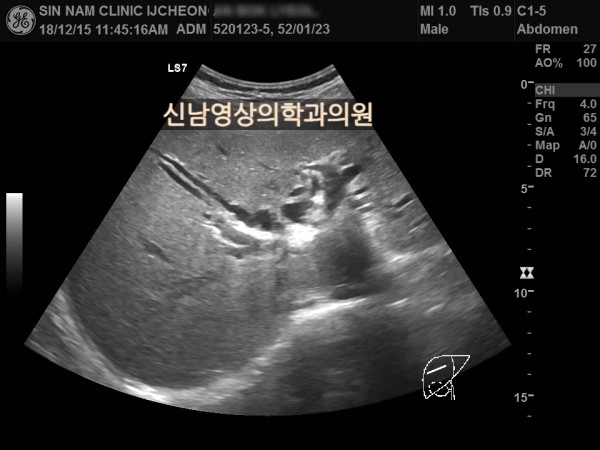

상복부검진

50~60대 발병률이 높은 담관암, 담도암, 상복부 초음파, 영상의학과 전문의